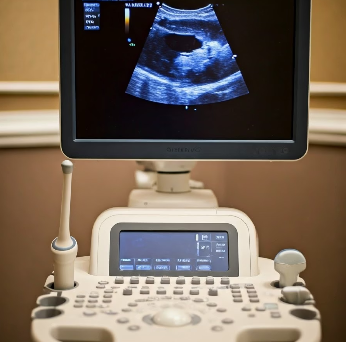

경동맥초음파는 목에 위치한 경동맥의 상태를 확인하는 비침습적 검사입니다. 초음파 기계를 이용해 혈류의 속도와 방향, 혈관 벽의 두께, 플라크 유무를 실시간으로 확인할 수 있어요.

이 검사는 방사선 노출이 없고, 10~15분 내외로 진행되며, 통증 없이 편안하게 받을 수 있습니다.